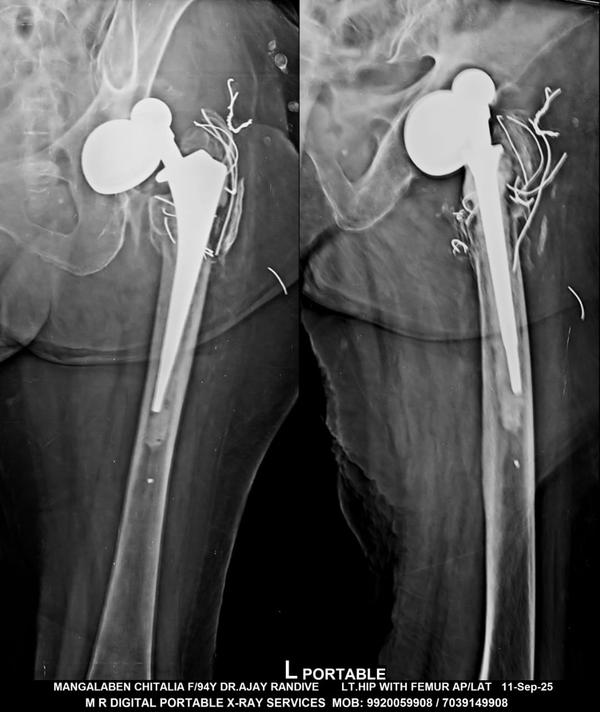

Dr Ajay Randive : IS MS Ortho (Mumbai) MRCSI ( UK) Consultant knee, Hip ,& Spine Surgeon, Dr Ajay Randhive is a eminent Knee, Hip , & Spine Surgeon practicing in to areas Andheri East,Santacruz East. Dr Ajay Randive did his MS Ortho residency from LTMMC, Sion Hospital Mumbai. He did overseas training in UK from 2003 till 2008. He is trained in total Knee Replacement, Hip Replacement, Revision Hip Replacement And Revision Knee Replacement Surgeries. He has worked at The Royal London Hospital. IN London where he worked a clinical fellow in joint Replacement unit. He has carried out more than 5000 Knee Replacement surgeries, 2500 Hip Replacement Surgeries, More Than 500 Revison Knee And Hip Replacement Surgeries 600 Spine surgeries & more than 1500 arthroscopic surgeries (Knee & Shoulder).